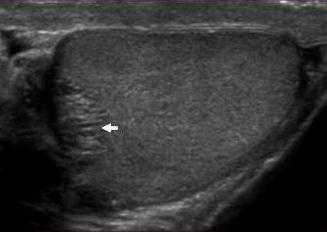

В норме яичко определяется как гомогенная структура овальной формы, эхогенность которой сравнима с эхогенностью щитовидной железы.

На первой картинке визуализируется гомогенная структура яичка в продольной плоскости. Текстура яичка такая же, как у щитовидной железы, представленной на втором изображении.

Белочная оболочка яичка на УЗИ представляет собой плотную полоску вокруг яичка. Яичко окружено влагалищной оболочкой, на УЗИ выглядящей как гипоэхогенное кольцо вокруг яичка. Висцеральная пластинка влагалищной оболочки прилежит к яичку и отделена от париетального листка тонким слоем серозной жидкости.

На данном изображении представлен срез яичка в поперечной плоскости. Яичко визуализируется как гомогенное образование, окруженное гипоэхогенным кольцом фиброзной ткани. Это кольцо является влагалищной оболочкой, содержащей между своими листками небольшое количество жидкости.